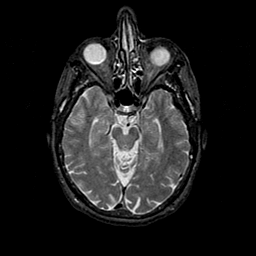

Normal Aging: MRI/SPECT overlay -- Slice #20

[Home][Help][Clinical] Slice 20